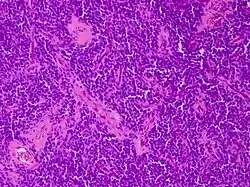

Micrograph of an H&E stained section of a peripheral PNET. | |